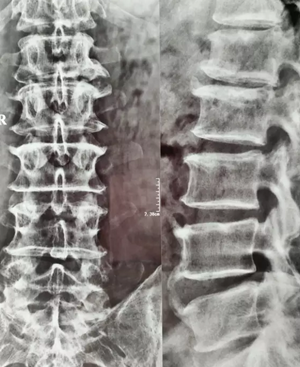

(术前)

来到我院后,经过再次详细问询及查体,他被诊断为“腰椎间盘突出症”。胡玉华院长为他制定了详细的手术方案。

10月7日上午9点,王先生被推入手术室开始手术。由胡玉华院长、李龙付副主任为他进行“腰4/5 、腰5/骶1椎间盘突出症+全椎板切除减压钉棒融合内固定术”。手术过程中并未出现状况,3个半小时以后,手术顺利的完成了。随即被送入了ICU病房进行监护。经过一段时间的护理,王先生已经恢复的很好了。